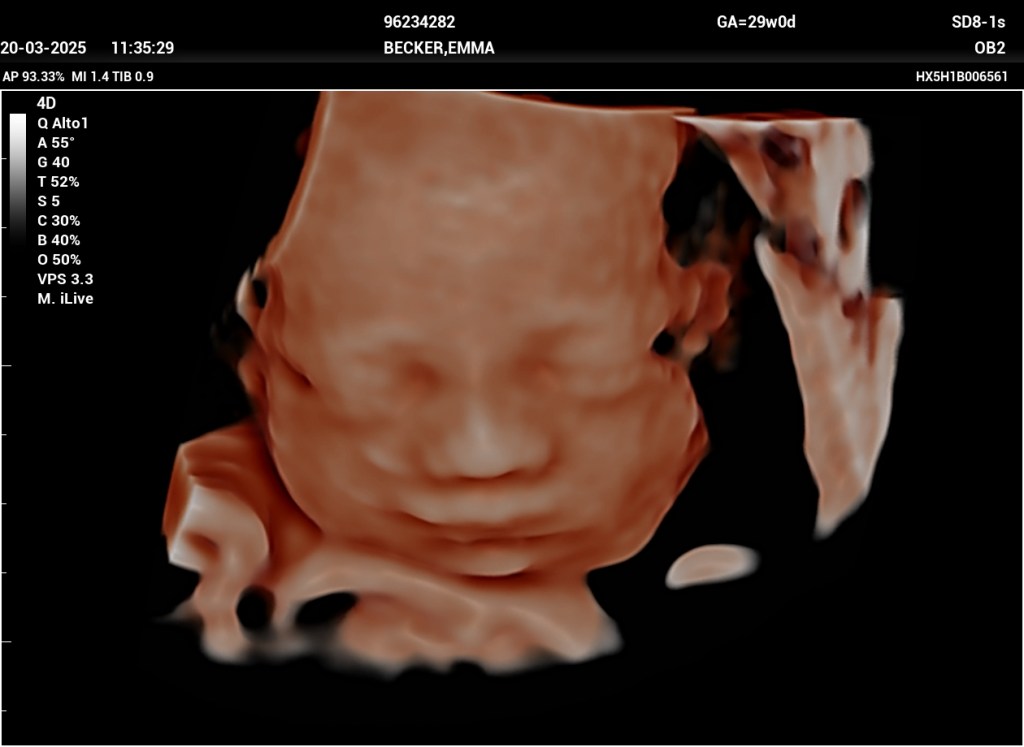

As we mentioned in our last letter, we arrived safely back in Argentina on March 5. We have been adjusting well back into Spanish and life here. We are so grateful for the friends here who have made it much easier to transition back. We have enjoyed getting to attend Iglesia Bautista Victoria again. We dove right into house hunting and have Lord-willing found a house. We have made good progress on being able to rent it and are now waiting on the realtor to hopefully let us know when we can sign the contract. We are also grateful that we found a doctor for Emma and have gotten her established and caught up on everything they need. The pregnancy has been progressing well and Emma and the baby are healthy. We are getting very close and are hoping to be able to get moved into our new house and settled soon.

- Healthy pregnancy and delivery of our baby girl.

- Iglesia Bautista Victoria 2. Friday night pizza with friends 3. The girls playing “church” 4. Sweet baby girl